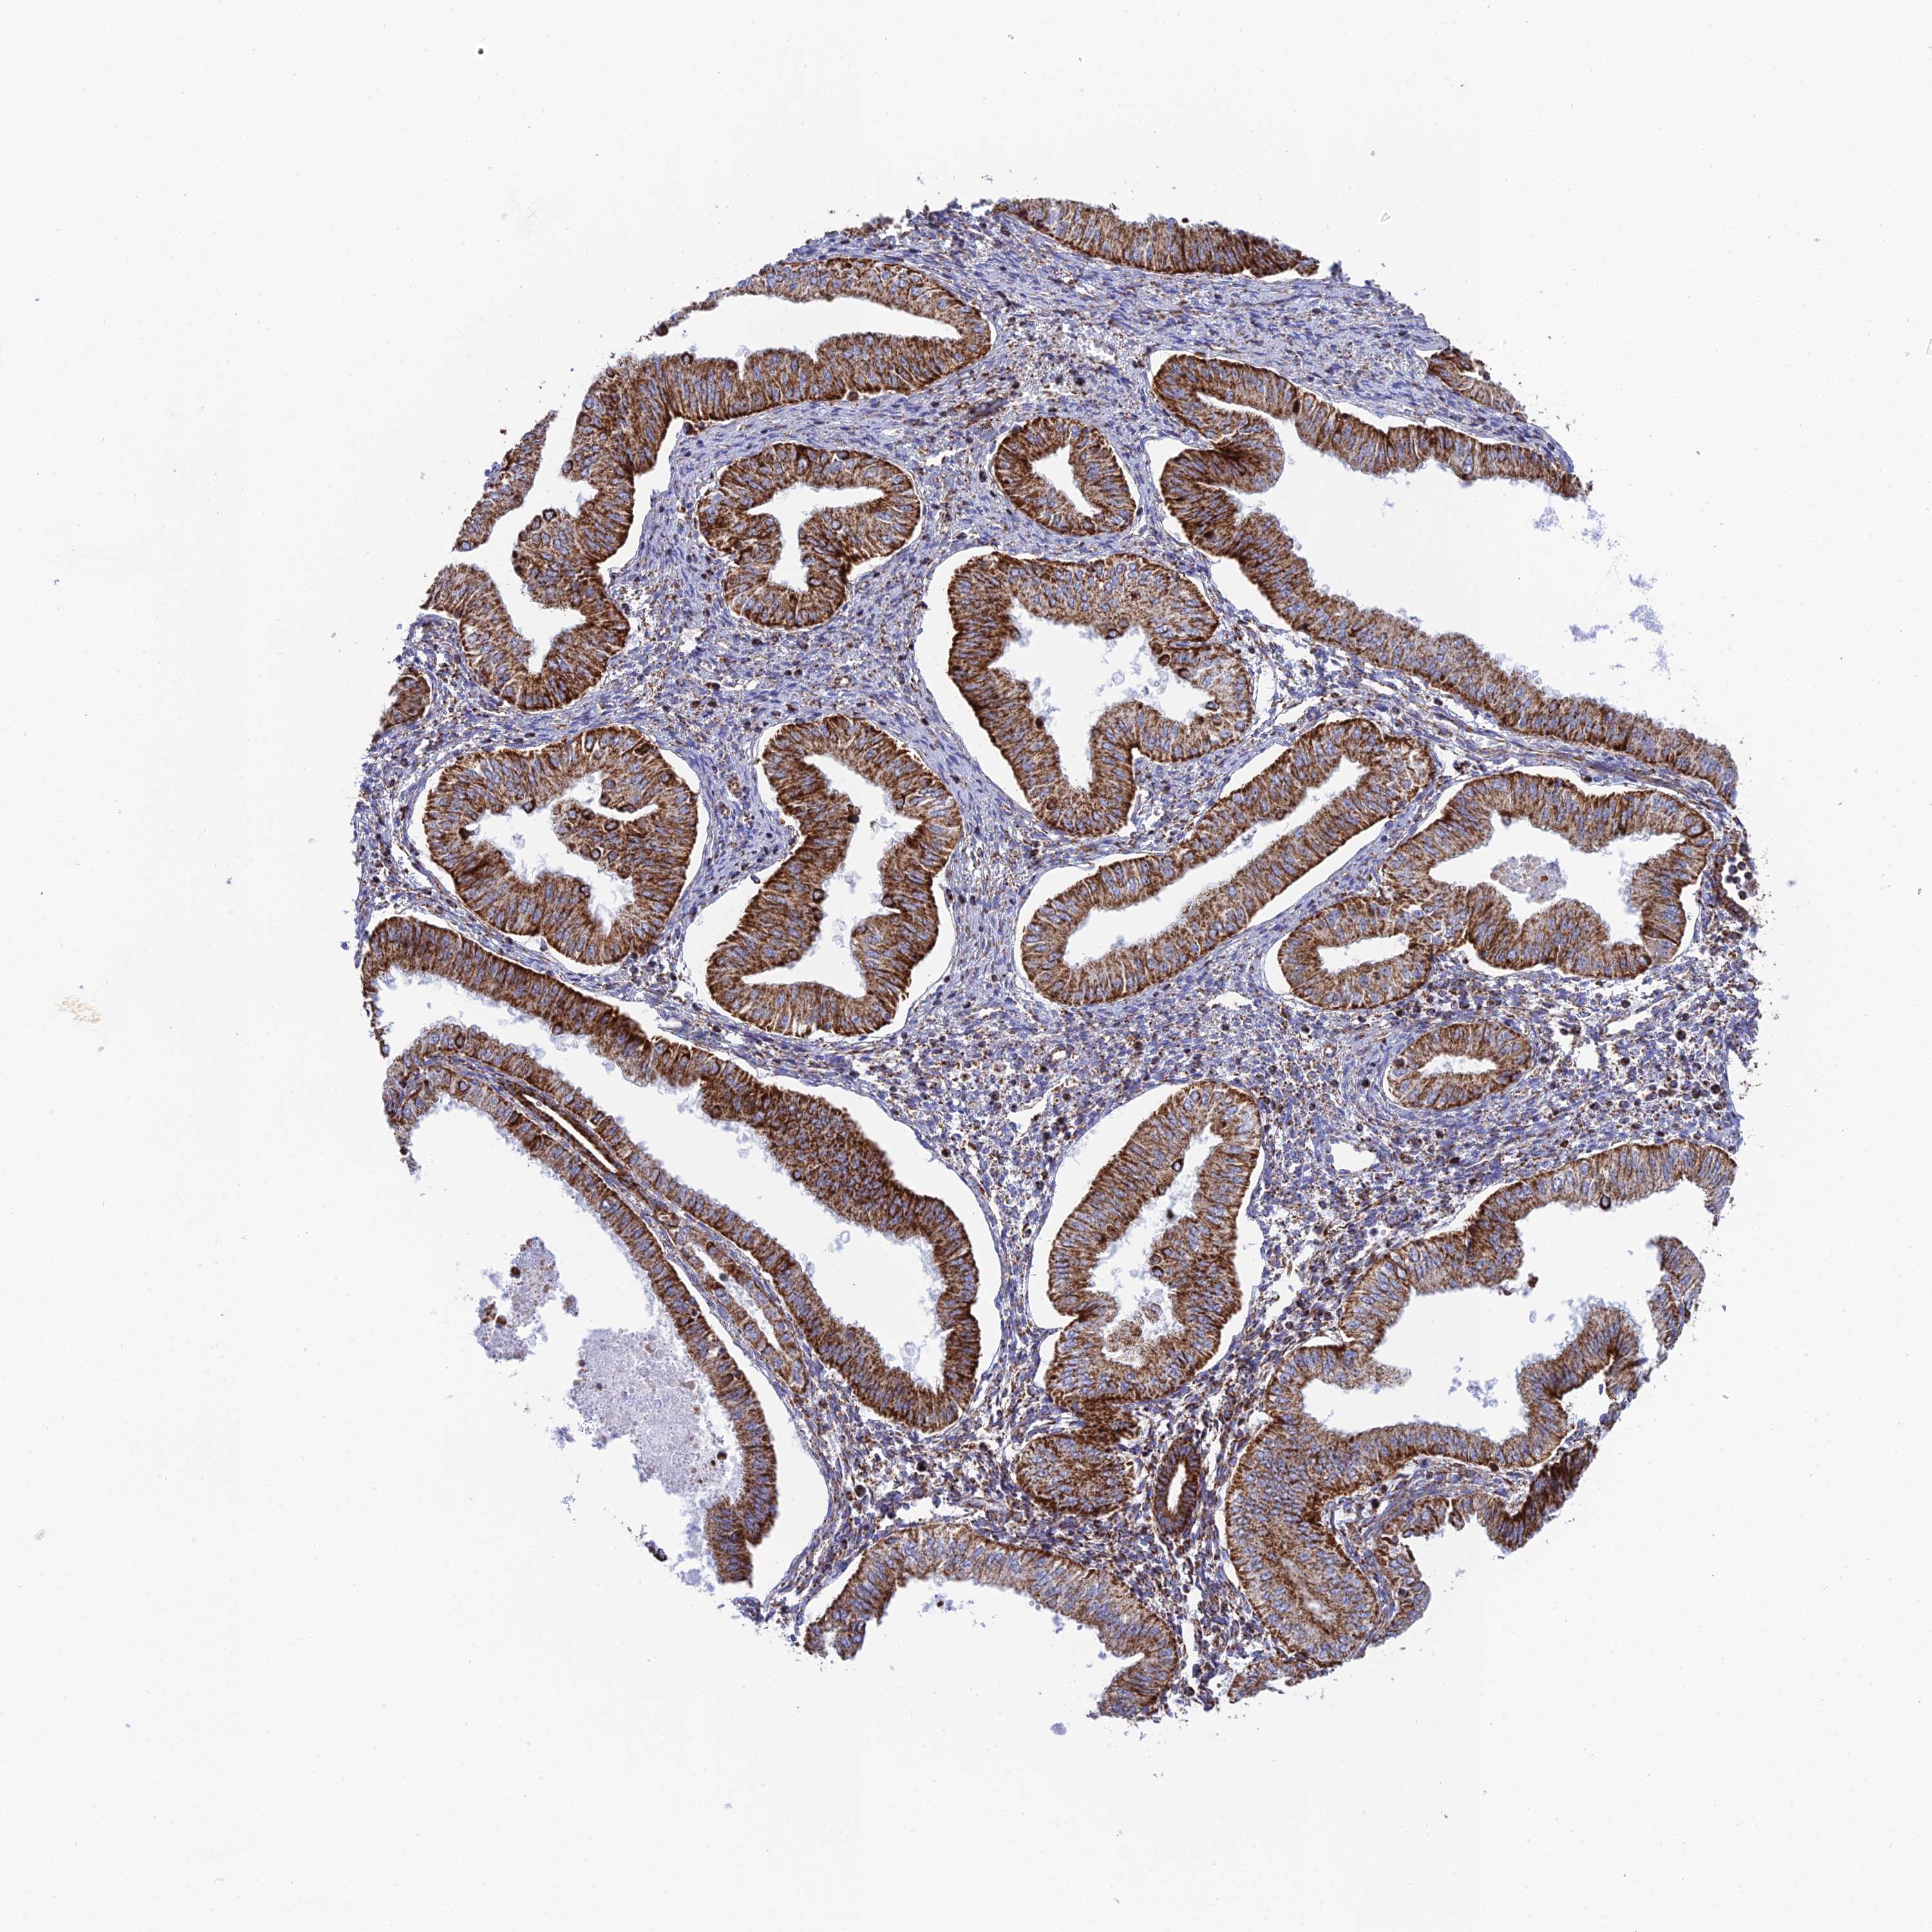

ENDOMETRIAL CANCER - Protein expressioni

A mouse-over function shows sample information and annotation data. Click on an image to view it in a full screen mode. Samples can be filtered based on level of antibody staining by selecting one or several of the following categories: high, medium, low and not detected. The assay and annotation is described here.

Note that samples used for immunohistochemistry by the Human Protein Atlas do not correspond to samples in the TCGA dataset.

Antibody stainingi

Antibody staining in the annotated cell types in the current human tissue is reported as not detected, low, medium, or high, based on conventional immunohistochemistry profiling in selected tissues. This score is based on the combination of the staining intensity and fraction of stained cells.

Each image is clickable and will lead to virtual microscopy that enables deeper exploration of all samples and also displays staining intensity scores, fraction scores and subcellular localization as well as patient and tissue information for each sample.

Antibody HPA042935

Staining

High

Medium

Low

Not detected

Intensity

Strong

Moderate

Weak

Negative

Quantity

>75%

75%-25%

<25%

None

Location

Nuclear

Cytoplasmic/membranous

Cytoplasmic/membranous,nuclear

Adenocarcinoma, NOS

Adenocarcinoma, metastatic, NOS